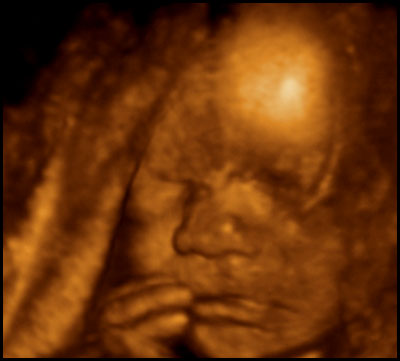

First, some notes on what you're seeing, in case some of these graphics seem a little weird. The machine only captures 3D images in a small area, and anything outside the area is either not visible or appears as blurriness. Also, while the technician tried for a good face shot, the baby's head was partially smooshed against the placenta the whole time, so it was never possible to get a really clear eyes/nose/mouth image.

Anyway, here he is....toes and all.

You guys. That's my SON in there! My god, I can't wait to meet him.